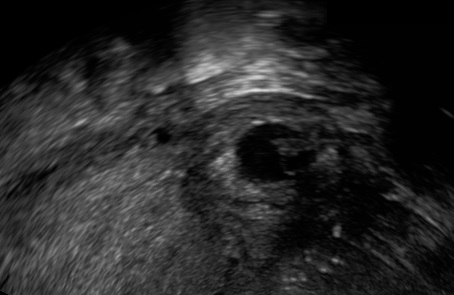

The following ultrasound criteria may be used for the diagnosis of interstitial pregnancy: empty uterine cavity, products of conception/gestational sac located laterally in the interstitial (intramural) part of the tube and surrounded by less than 5 mm of myometrium in all imaging planes, and presence of the ‘interstitial line sign’ (Elson CJ et al., 2016).